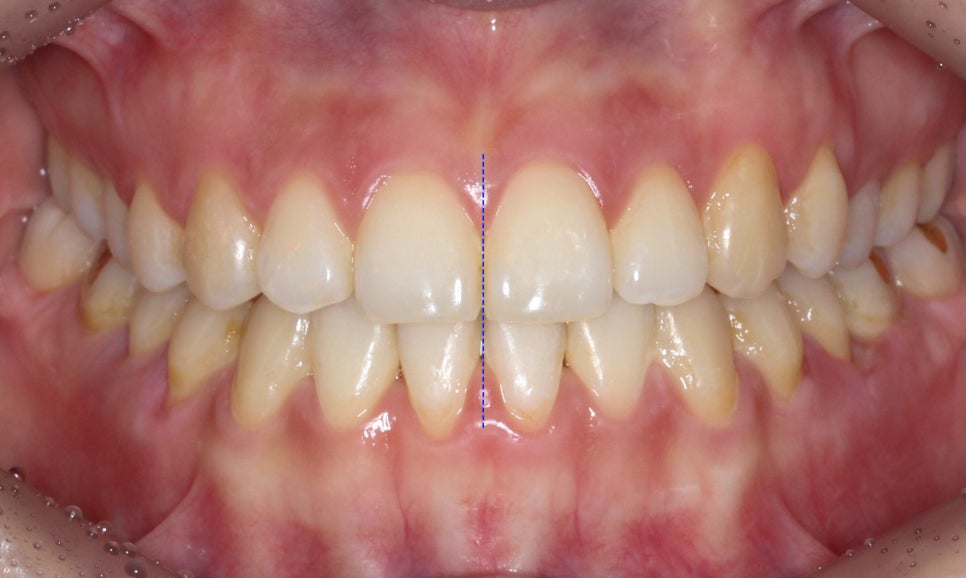

전체교정 후

절단교합 교정 후 정면 구내 사진입니다.

상악과 하악 모두 최후방의 사랑니를 발치하여

치아가 배열될 수 있는 공간을 확보하였는데요,

전치부의 교합을 바로잡고 구치부 부정교합을

바른 교합 상태로 만들기 위해서 경우에 따라

사랑니가 아닌 소구치를 발치해야 할 수 있기 때문에

치아교정 전 반드시 교정전문의와 상담이 필요합니다.

클리피씨 교정 후 전치부의 overbite 수치를 보면

교정 전과 달리 상하악이 바르게 교합되는

모습을 확인할 수 있는데요,

교정 전 부정교합으로 인해 전치부의

수직피개가 0에 가까웠다면

교정 후 약 2mm정도로 개선된 모습입니다.

교정 후 전치부의 절단교합 증상이

많이 완화된 모습으로 overjet 사진에서

바른 교합 상태를 확인할 수 있는데요,

교합평면도 좌우 모두 클리피씨 교정 후

어금니의 교합이 바르게 교정된 모습입니다.